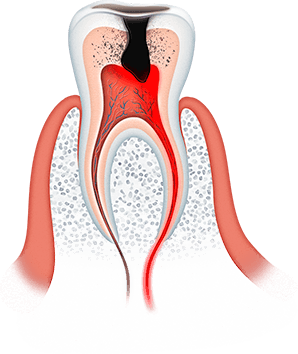

Большинство стоматологических заболеваний необратимые

Важно помнить, что большинство стоматологических заболеваний необратимые, кариозная полость сама по себе не зарастает, костная ткань при пародонтите не восстанавливается, а утраченные зубы не вырастают заново. Болезни полости рта при отсутствии своевременного лечения прогрессируют: кариес превращается в пульпит, пульпит в периодонтит, последний очень часто приводит к потере зуба.